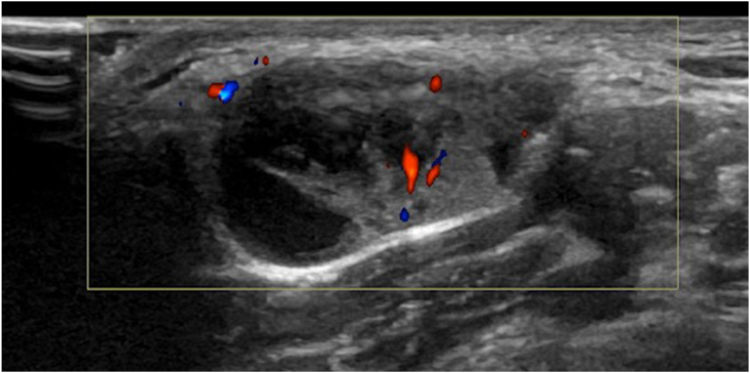

Our case describes a 24-year-old woman who initially presented with a right lateral neck lump. This was thought to be a lipoma, and no workup was performed until it began to grow during pregnancy 3 to 4 years after initial presentation. The patient underwent excision with findings of a level 5B lymph node with pathology consistent with PTC, follicular variant. Neck ultrasound performed in an imaging center and in our clinic did not reveal thyroid nodules or abnormal appearing lymph nodes. Solid tumor profiling assay identified a neurotrophic tropomyosin receptor kinase (NTRK)-3 fusion: ETV6(4)-NTRK3(14) mutation.